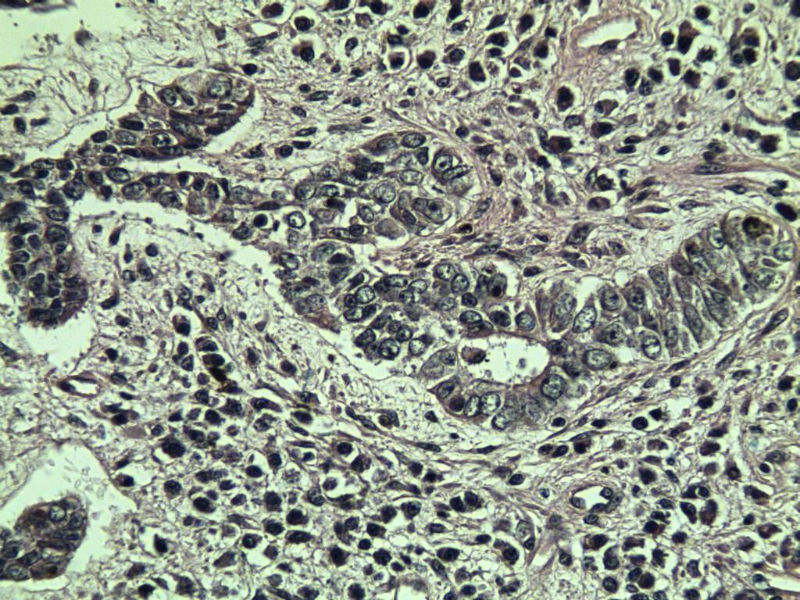

这是另外一个  75岁 男性 脸上有一直径0.8cm新生物 是鳞癌吗? 感觉细胞异型性不够大.

第二例:基底细胞癌

第二例,两种成分,1、毛发上皮瘤;2、皮内痣。

第一例考虑毛母细胞瘤,第二例考虑基底细胞癌。

第一例:毛母细胞瘤;第二例:基底细胞癌

第一例,毛发上皮瘤;第二例,基底细胞癌。

1.BCC.  2.BCC.

二基底细胞癌。

两例均为BCC